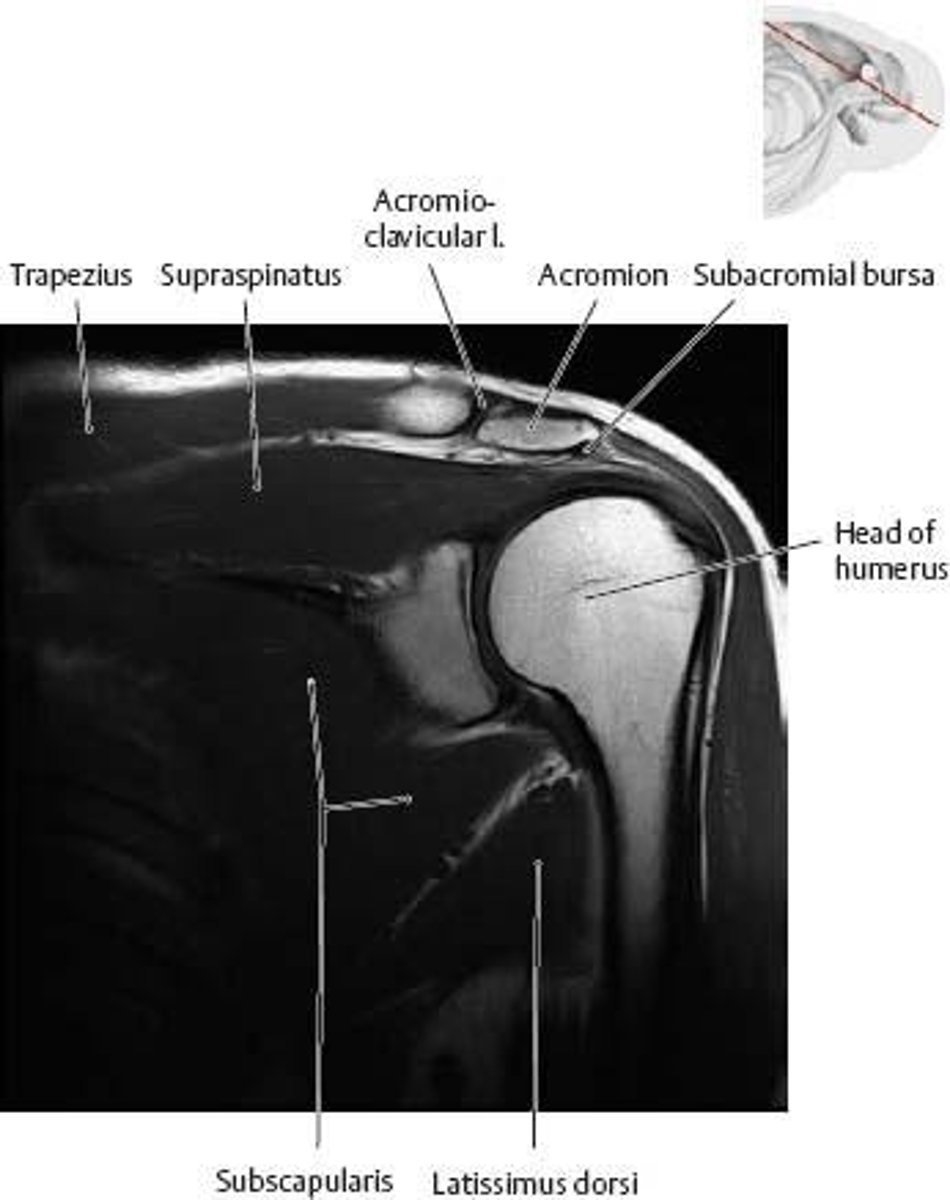

Which nerve innervates the supraspinatus muscle?

Suprascapular nerve (C4-C6)

What is the role of the rotator cuff muscles?

To maintain the stability of the shoulder joint

What is the function of the infraspinatus muscle?

Lateral rotation of the arm

What is the innervation of the subscapularis muscle?

Upper and lower subscapular nerves (C5, C6, C7)